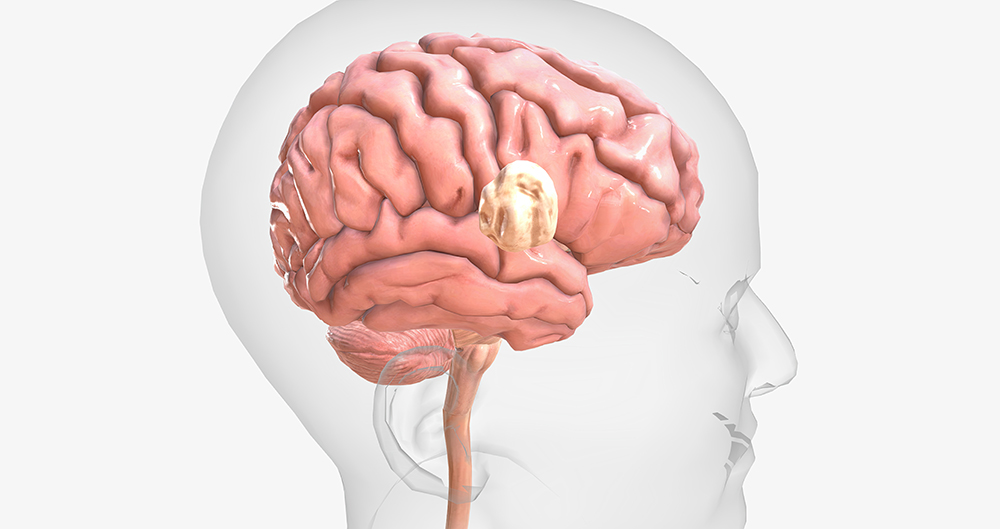

모야모야병은 뇌의 주요 혈관, 특히 내경동맥과 이를 따라 뻗어 있는 뇌혈관이 점차 좁아지면서 비정상적인 혈관이 생기는 질환입니다. 이러한 비정상 혈관은 뇌로 가는 혈류를 보충하려는 대체 혈관 역할을 하지만, 쉽게 파열되거나 혈류가 부족해지는 문제를 일으킵니다.

‘모야모야’는 일본어로 ‘뿌옇게 보인다’는 뜻으로, 뇌혈관 조영술에서 혈관이 비정상적으로 얇아져 희미하게 보이는 것을 비유한 이름입니다. 이 병은 유병률이 비교적 낮지만, 동아시아에서 특히 많이 나타나는 것으로 보고됩니다.